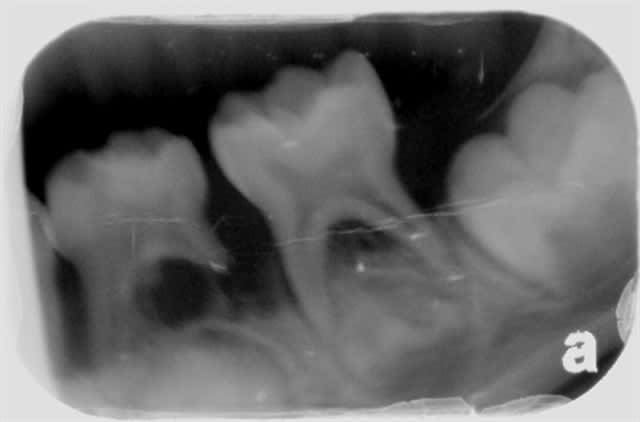

Sans compter que si on se lasse de la paro de l'adulte, on peut toujours passer à la paro de l'enfant :

Paro p do 1 fvzzcp - Eugenol

Paro p do 2 udoc3y - Eugenol